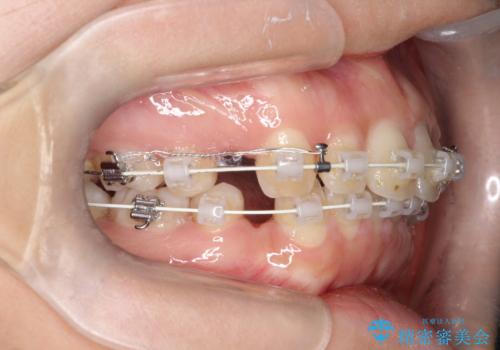

- 矯正装置

- 審美装置

- 治療期間

- 9ヶ月